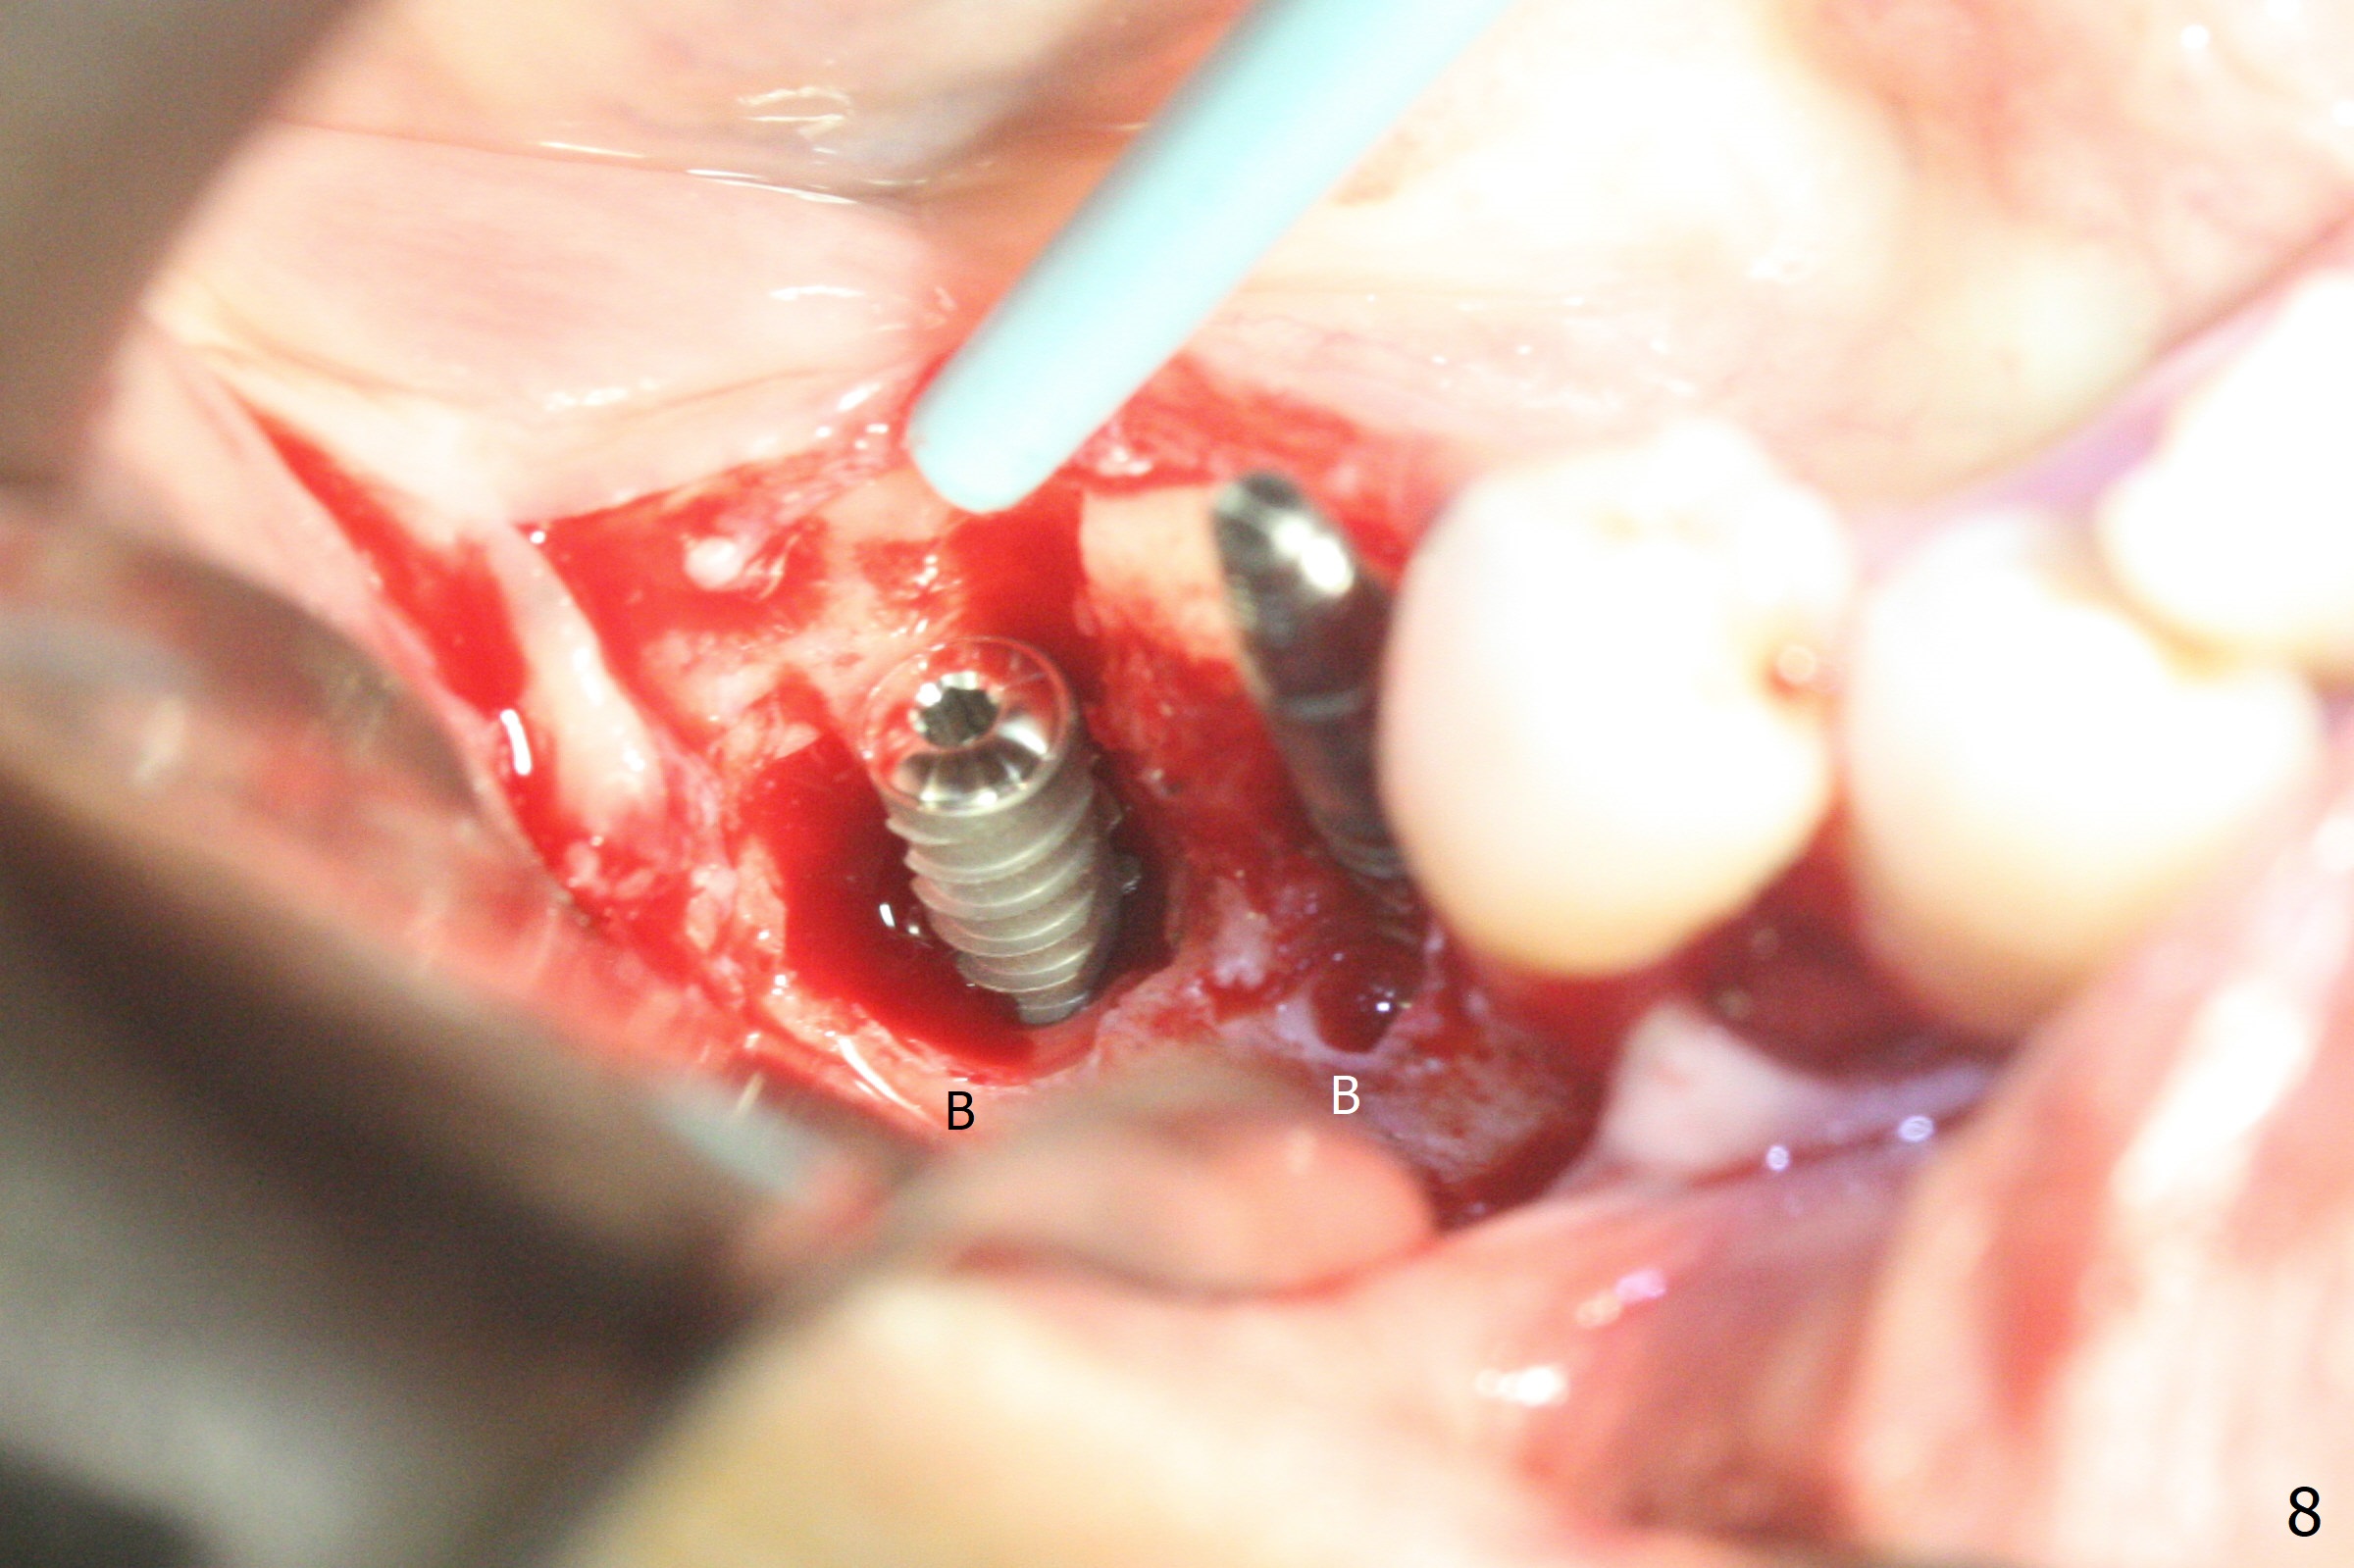

The implant at #30 was also buccally placed (Fig.6,7) and should be corrected in the same manner (Fig.7 green). Due to the bone being harder in the molar region, a smaller and shorter implant (4x11 mm vs. 5x13 mm) shifts slightly buccally while being placed (Fig.8,9). Since primary stability is lower (<20 Ncm vs. 35 Ncm associated with the implant #29), an abutment is not placed, which may be favorable to healing, but it is difficult to achieve primary closure. After bone graft (Fig.9 *) and 2 layers of PRF, Cytoplast is placed. Cytoplast appears to be exposed buccally (Fig.10 <) and occlusally (Fig.11 ^) asymptomatic 9 days postop. Exposure of Cytoplast is more distinct without sign of infection 15 days postop (Fig.12). The patient returns with chief complaint of "foul smell" 7 weeks postop (coronavirus lockdown). Although the Cytoplast exposes more (Fig.13 (* exposed; @ unexposed)), the underlying gingiva remains healthy (Fig.14). While the bone height decreases at #29, the bone density at #30 increases 4.5 months postop (Fig.15). The gingiva heals. The implant at #30 is uncovered 6 months postop. The lingual plate has to be removed for the uncover, while the coronal end of the buccal one is missing. No bone graft is added. When the 4.5x4 mm healing abutment is removed 6.5 months postop, the buccal plate looks concave at #30 (Fig.16' *). The buccal plate looks thin at #29 with a cotton roll placed buccally (Fig.16 R). The lingual plate at #29 is coronal to the buccal one (Fig.17). The buccal gingiva at #29 is quite long (Fig.18). The coronal buccal plate appears to be missing (Fig.19 >), which will be watched. A 4.5x7.5(4) mm cemented abutment is torqued (Fig.20).